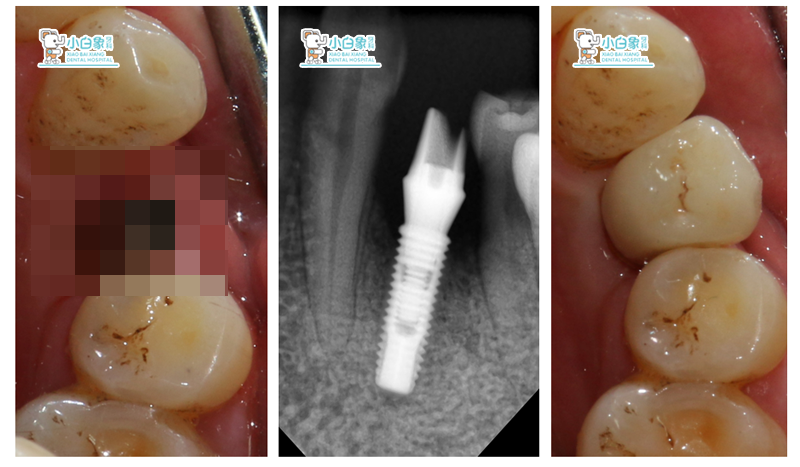

图片1

检查:颌面部未见异常,口内查:34缺失,牙槽骨低平,牙龈无红肿。

CBCT:34颊侧骨缺损。

诊断:下牙列缺损。

治疗方案:34植骨+美格真种植修复。